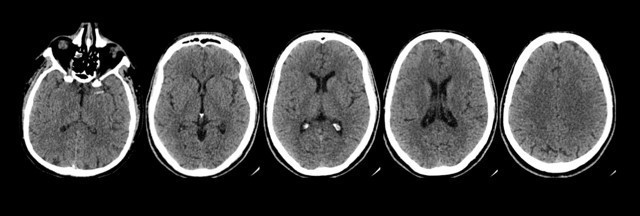

L’imagerie suivante est réalisée en urgence. L’ECG est en ACFA.

Les corticales osseuses sont « blanches », il s’agit donc d’un scanner cérébral.

Absence de visualisation de produit de contraste dans les structures vasculaires, il s’agit donc d’un scanner cérébral sans injection.

Question 9: Vous constatez sur le scanner sans injection

Sur ce scanner sans injection, on n’observe aucune anomalie parenchymateuse. En revanche, on observe une hyperdensité spontanée de l’artère cérébrale moyenne gauche dans son segment proximal, correspondant à un thrombus.

Cela est parfaitement compatible avec le diagnostic d’infarctus cérébral sylvien gauche à la phase très aiguë.